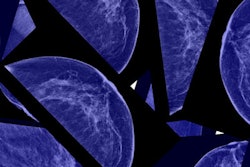

The American College of Radiology (ACR) has released an updated version of its 2016 Digital Mammography Quality Control Manual.

The manual helps users develop and implement quality control (QC) programs for digital mammography equipment, and it outlines the responsibilities of radiologists, radiologic technologists, and medical physicists, according to the college.